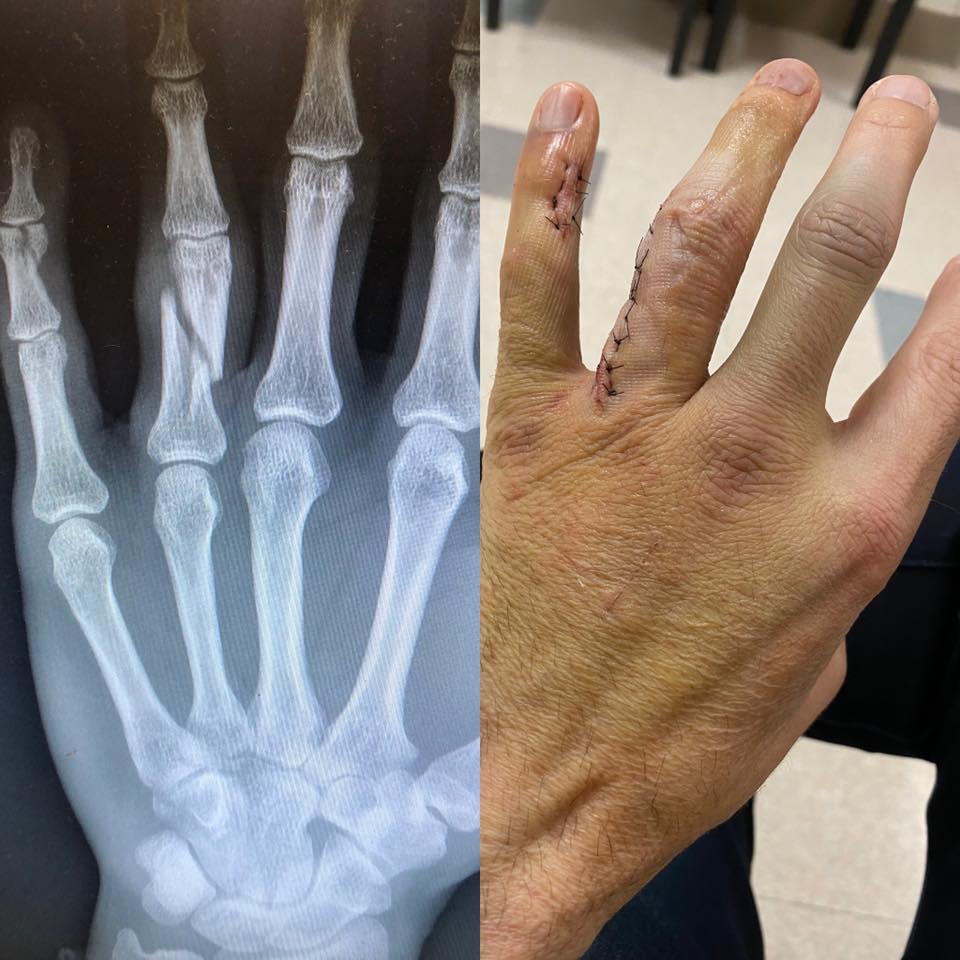

Kisebb balesetet szenvedett Jerry Horton, a Papa Roch gitárosa, ennek következtében kénytelen kihagyni a banda hamarosan induló európai turnéját.

Különösebb magyarázatot nem fűzött röntgenfelvételéhez Jerry Horton, mellyel azt tudatta, hogy kénytelen kihagynia a csapat hamarosan startoló európai koncertkörútját. A gitáros két ujját törte el, így helyettessel, Anthony Esperance gitáros-billentyűssel kel útra a Papa Roach.